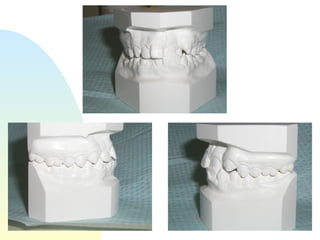

Patient   : J.R, male DOB :7/20/91, start of tx age: 12yr 9mo Ethnicity : American-born Hispanic, English-speaking Health Hx :  WNL, unremarkable Dental Hx :TMJ=WNL, OH=B+, midline=on, molar R&L= Cl 1, OB=40%, OJ= 1mm, dental anterior cross-bite, crowded max & mand anteriors, caries #15-O, #18-O,B, perio=WNL Psychosocial : Parents are separated,  1 younger sister,1 older sister.  Mom had ortho tx --- 4 premolars & 4-3rd molars extracted, “My braces hurt and I don’t want a lot of teeth pulled on my son”. Chief complaint :  “I don’t like the way my teeth stick out in front.”

31.6 35.7 44.4 42.3 29.6 Schwarz analysis SI=31.6, Max 4-4’s ideal = 39.6   actual 35.7 difference= -3.9 Max 6-6’s ideal= 47.6 actual 44.2 difference= -3.2  total -22.4 Man 4-4’s ideal= 39.6 actual 29.6 difference= -10 Man6-6’s ideal= 47.6 actual 42.3 difference= -5.3

31.6 35.7 44.442.3 29.6 Schwarz analysis SI=31.6, Max 4-4’s ideal = 39.6 actual 35.7 difference= -3.9 Max 6-6’s ideal= 47.6 actual 44.2 difference= -3.2 total -22.4 Man 4-4’s ideal= 39.6 actual 29.6 difference= -10 Man6-6’s ideal= 47.6 actual 42.3 difference= -5.3